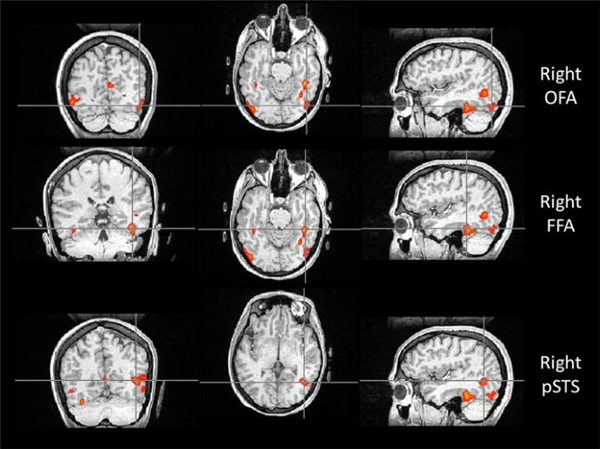

你能记住多少张脸?研究发现,人类平均能记住约 5000 张面孔(波动范围约为1000~10000),这一能力在自然界中无可比拟。而大多数动物识别同类主要依赖气味或声音,而不是脸。一些高度社会化的家畜,比如绵羊,在经过特殊训练后能记住大约 50 张羊脸,仅有人类的百分之一。除了人类以外的其他灵长类,识脸能力在动物界也属于佼佼者,但数量多在数十到上百张之间,目前仍缺乏确切的上限数据。为什么人类拥有如此出众的“认脸”能力呢?人类拥有与生俱来的“认脸系统”这是因为人脑中存在一套专门“...